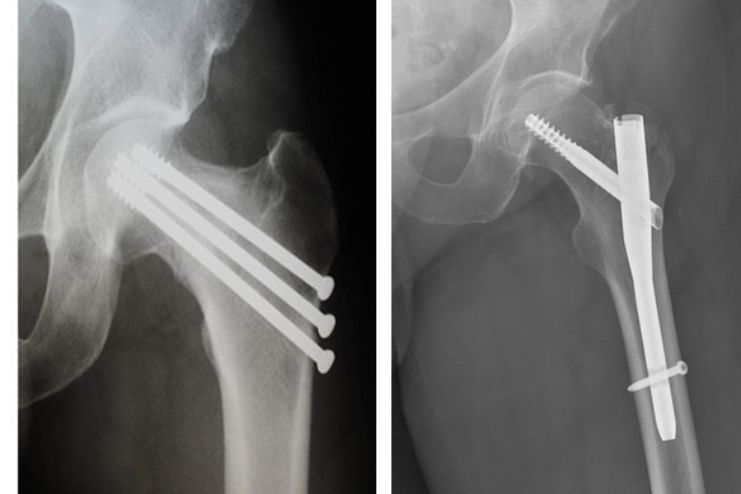

తుంటి ఫ్రాక్చర్ కు శస్త్రచికిత్స Surgery for Hip Stress Fractures

పగులు స్థానభ్రంశం చెందుతుందనే ఆందోళన ఉంటే శస్త్రచికిత్స అవసరం. పగులు గణనీయంగా ఉండి, తొడ మెడపై ఉంటే, అది స్వయంగా నయం కావడానికి తక్కువ అనుకూలంగా ఉంటే ఇది తరచుగా పరిగణించబడుతుంది. పగులు యొక్క నిర్దిష్ట స్థానం మీ ఆరోగ్య సంరక్షణ ప్రదాత ఉత్తమ చికిత్సను నిర్ణయించడంలో సహాయపడుతుంది. కుదింపుకు దారితీసే తుంటి ఒత్తిడి పగుళ్లు ఎముక ఉద్రిక్తతలో ఉన్న చోట సంభవించే వాటి కంటే స్థిరంగా ఉంటాయి. ఎక్స్-రే మరియు MRI ఫలితాల ఆధారంగా ఒత్తిడి పగులు స్థిరంగా ఉందో లేదో మీ వైద్యుడు నిర్ణయించవచ్చు.